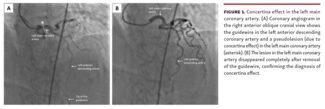

Concertina effect in the left main coronary artery after percutaneous intervention should be considered in the appropriate setting to avoid confounding management dilemmas and unwarranted interventions.